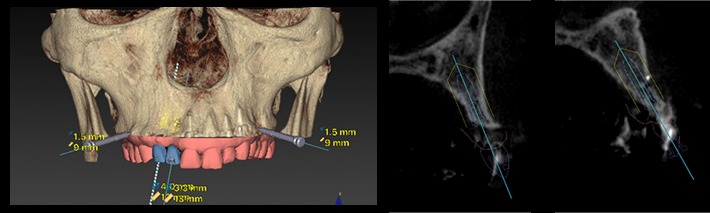

Nobel Clinician によるシミュレーション

ガイデッドサージェリー